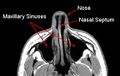

حاجز الأنف أو الوتيرة (بالإنجليزية:nasal septum) هو الجدار الذي يفصل جوف الأنف إلى قسمين متناظرين. يتركب من قسم غضروفي يشكله غضروف حاجز الأنف وقسم عظمي يشكله كل من الميكعة والصفيحة العمودية للعظم الغربالي. يغطى حاجز الأنف في كل جانب بمخاطية الأنف.